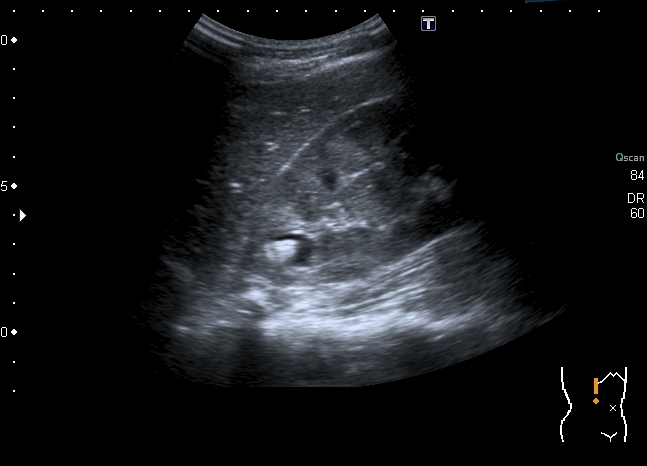

Скан области интереса

Полость в врехнем полюсе, но на Фрейли не похоже - нет сосуда на ЦДК под полостью. Была мысль о дивертикуле чашечки, будем дообследовать путём экскреторной урогфии, изображения выложу.KapustinSV писал(а):Cлева "голова" или справа?

Мальчика выписали без рентгенологического исследования. Будем обходиться УЗИ. Почему это не может быть кистой с конкрементами? Формирование конкрементов в кисте менее вероятно, чем в дивертикуле чашечки или в расширенной чашечке при синроме Фрейли. Но полость уж больно круглая, да и связи с ЧЛС и конфликта с интраренальным сосудом сколько не смотрел, я не увидел.